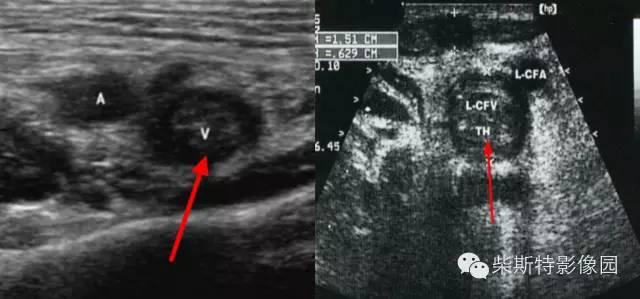

6. 加压静脉超声成像

加压静脉超声成像(CUS)可发现 95% 以上的近端下肢静脉内血栓,故一般我们首选 CUS 诊断 DVT。静脉不能被压陷或静脉腔内无血流信号为 DVT 的特定征象和诊断依据(图 7)。

图 8. CUS 示意图(CFA: 股总动脉;CFV:股总静脉;GSV:大隐静脉;LT:左侧(图片来自哈里森内科学 20 版))

下肢深静脉超声

下肢深静脉超声:红色箭头所指为血栓(纵切面)

下肢深静脉彩色多普勒CDFI:红色箭头所指为血栓(纵切面)